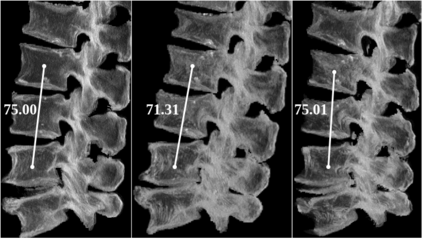

Symptomatic spinal vertebral compression fractures (VCFs) often require osteoplasty treatment. A cement-like material is injected into the bone to stabilize the fracture, restore the vertebral body height and alleviate pain. Leakage is a common complication and may occur due to too much cement being injected. In this work, we propose an automated patient-specific framework that can allow physicians to calculate an upper bound of cement for the injection and estimate the optimal outcome of osteoplasty. The framework uses the patient CT scan and the fractured vertebra label to build a virtual healthy spine using a high-level approach. Firstly, the fractured spine is segmented with a three-step Convolution Neural Network (CNN) architecture. Next, a per-vertebra rigid registration to a healthy spine atlas restores its curvature. Finally, a GAN-based inpainting approach replaces the fractured vertebra with an estimation of its original shape. Based on this outcome, we then estimate the maximum amount of bone cement for injection. We evaluate our framework by comparing the virtual vertebrae volumes of ten patients to their healthy equivalent and report an average error of 3.88$\pm$7.63\%. The presented pipeline offers a first approach to a personalized automatic high-level framework for planning osteoplasty procedures.